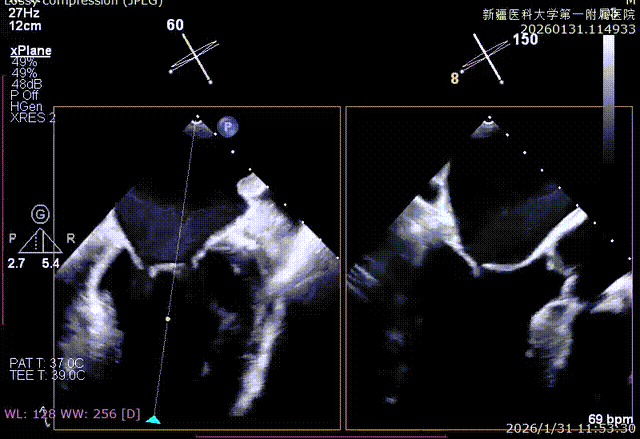

XPLAN后叶严重栓系

Bicom切面中重度反流

3D enface 观察后叶栓系

3D enface观察反流

房间隔成功穿刺